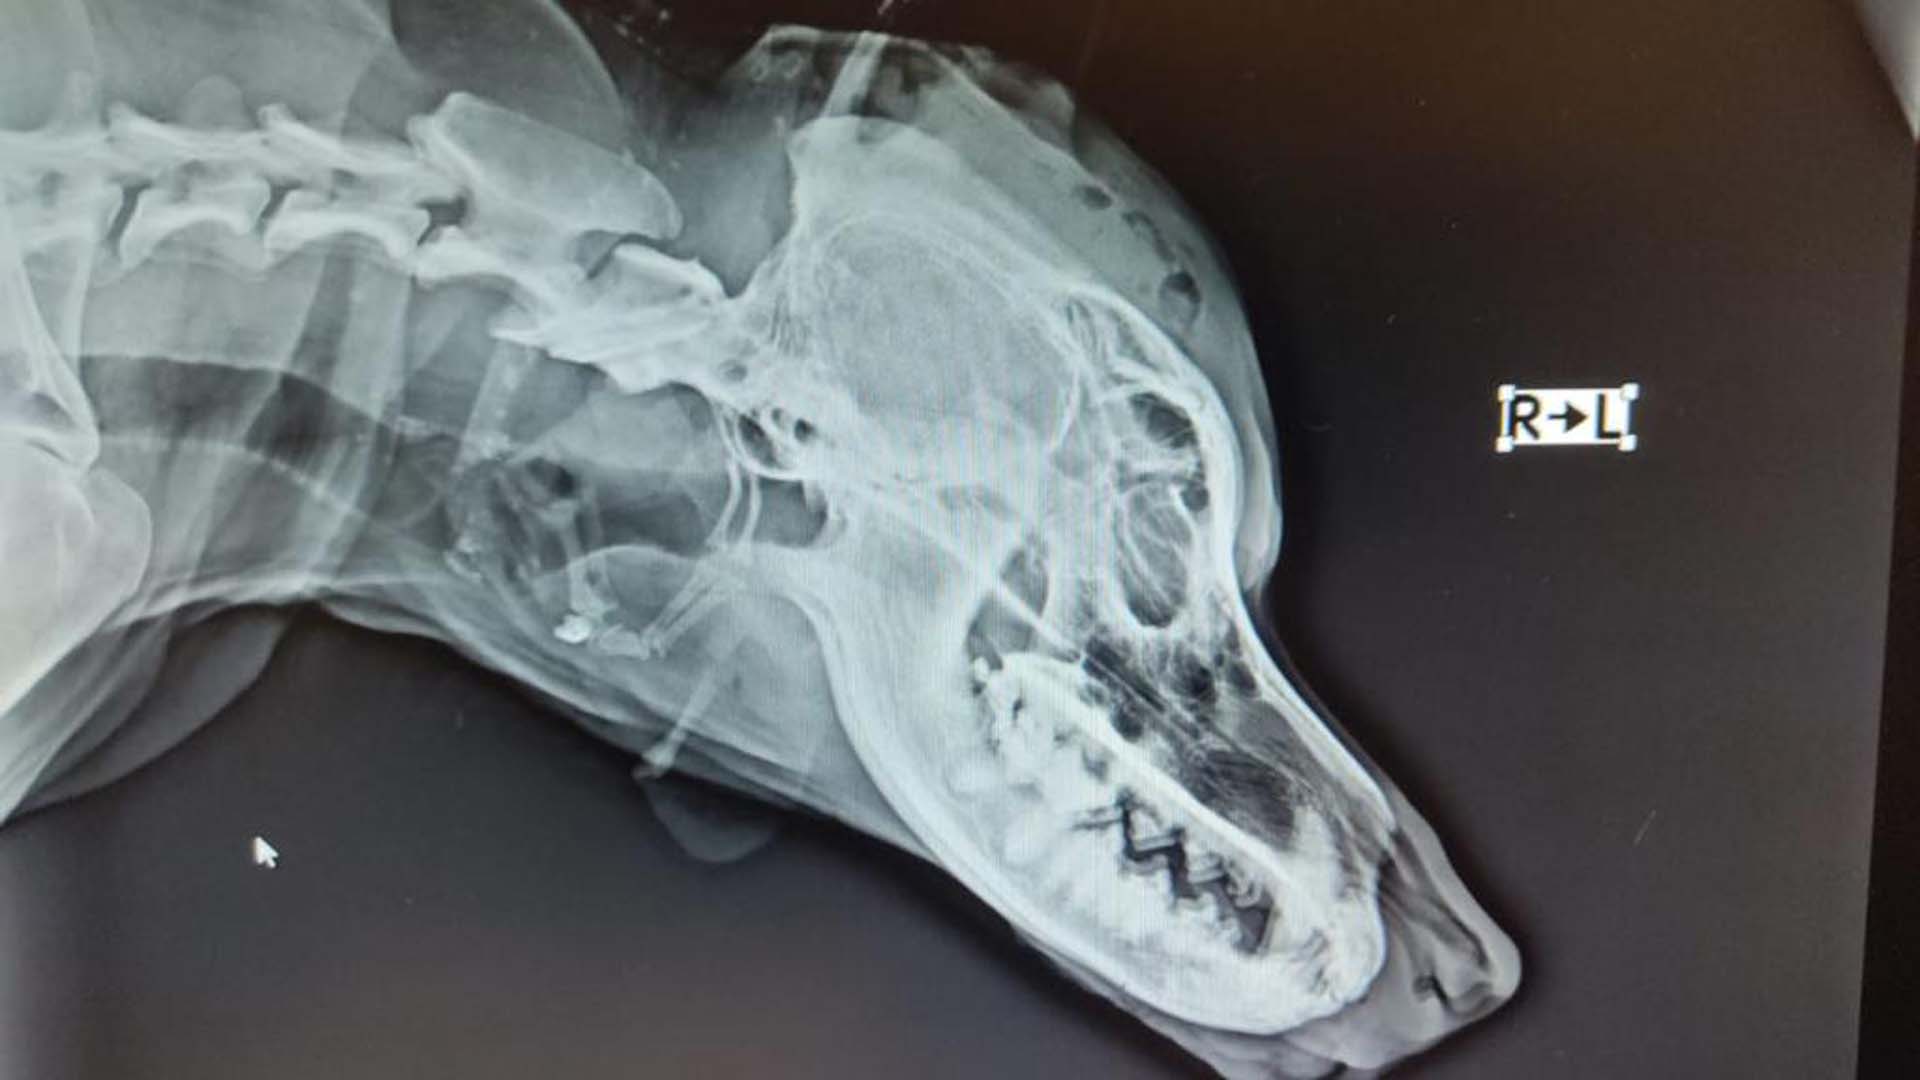

KAFATASINDA KIRIKLAR OLUŞTU

Kafatasında kırıklar olduğu belirlenen Duman, Sokak Hayvanlarını Koruma Yaşatma Rehabilitasyon ve Eğitim Derneği'nin yardımıyla, başka bir kliniğe götürülerek tedavi altına alındı.